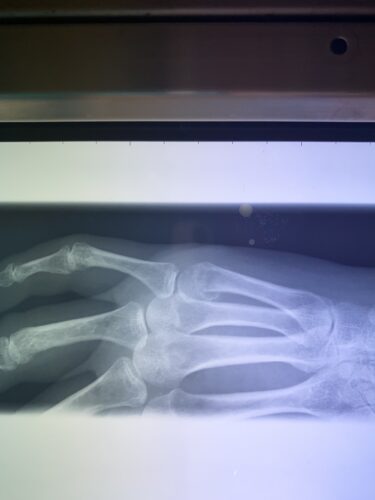

さわやか千葉県民プラザ(指骨骨折)